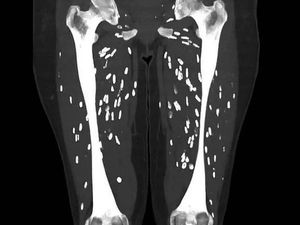

Sebuah foto rontgen mengerikan menunjukkan tubuh pasien dipenuhi larva cacing pita akibat mengonsumsi daging babi mentah.